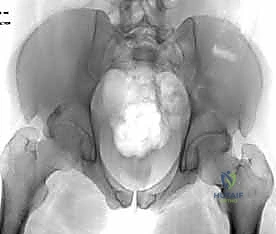

عند حدوث قوة قاهرة تفوق قدرة تحمل هذه الأربطة، يتمزق المفصل وتنفصل عظام العانة عن بعضها، وهو ما يُعرف طبياً بـ "كسر الكتاب المفتوح" (Open Book Fracture) إذا تجاوز الانفصال 2.5 سم. هذا الانفصال يؤدي إلى عدم استقرار كامل في الحلقة الحوضية.

يتم تقييم المريض بشكل شامل (أشعة سينية، أشعة مقطعية ثلاثية الأبعاد) لتحديد حجم الإصابة بدقة. تُجرى العملية تحت التخدير العام لضمان استرخاء العضلات بالكامل وعدم شعور المريض بأي ألم. يتم وضع المريض على ظهره على طاولة العمليات، وتُعقم منطقة البطن والحوض بالكامل.